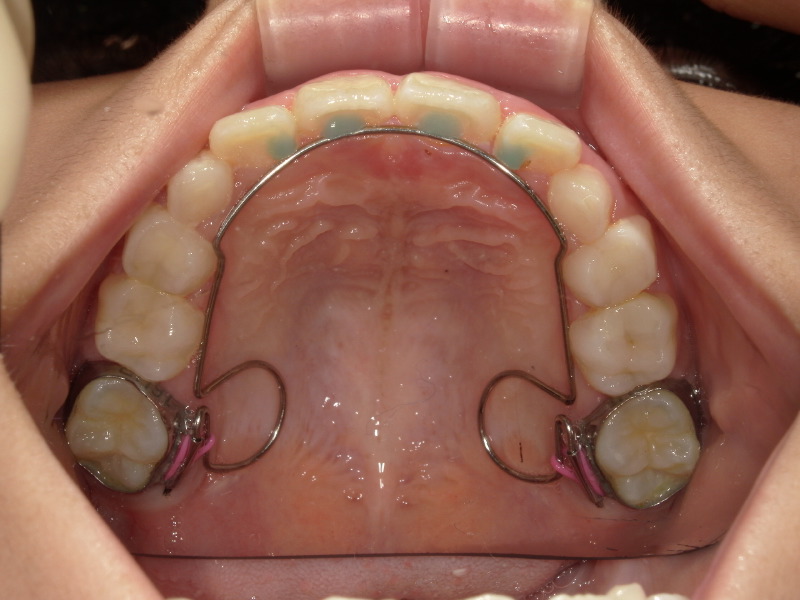

bwsの装着

タイミングをみて顎の成長を促すための装置をセットしました。

何ヶ月かかけて、歯を少しずつ押しています。

装着時とオフ前の写真ではかなり歯が開いています。